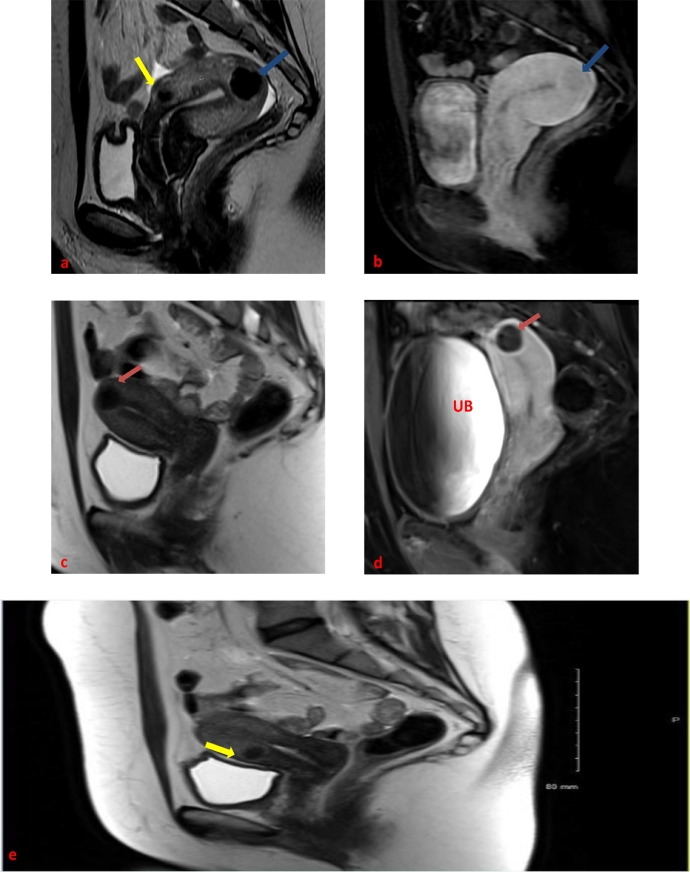

Forty-six-year old nulliparous female, status post prior myomectomy for dysfunctional uterine bleeding presented to our multidisciplinary uterine fibroid clinic with menometrorrhagia. Patient's preprocedural magnetic resonance imaging (MRI) revealed multiple intramural fibroids within an overall enlarged retroverted uterus measuring 9 cm × 6.3 cm × 5 cm. The largest fibroid which we termed the index fibroid was located within the uterine fundus and measured 2.3 cm × 2.1 cm × 2 cm. The second largest fibroid was located anteriorly and measured 1.8 cm × 1.7 cm × 1.5 cm. Both fibroids demonstrated post contrast isoenhancement compared to the background myometrium. Other much smaller intramural fibroids we also noted. (Fig. 1 a and b).

Fig. 1.

Forty-six-year-old female with multiple fibroids before and after embolization: pre-UFE T2-weighted (a) and postgadolinium T1-weighted (b) sagittal images showing an enhancing intramural fundal fibroid (blue arrows) within a retroverted uterus. An anteriorly located fibroid with similar imaging features can also be seen on pre-UFE imaging (yellow arrow). (For interpretation of the references to colour in this figure legend, the reader is referred to the web version of this article).

At our institution, patients undergoing UFE are given epidural patient-controlled analgesia post procedurally and admitted for 23-hour observation. In our case, the patient's subsequent hospitalization course was uneventful with well-controlled post procedural pain. The patient came back to our multidisciplinary clinic for her 6-month post UFE follow-up. She reported complete resolution of her original presenting symptoms, including her menstrual pain and heavy bleeding. Her 6-months post UFE contrast enhanced MRI images showed complete devascularization and shrinkage of her fibroids with overall decrease of uterine volume from 9 cm × 6.3 cm × 5 cm down to 7.2 cm × 4.8 cm × 3.2 cm. The index fibroid located in the uterine fundus had an estimated volume decrease from 5575 mm3 down to 2144 mm3. Interestingly, the anteriorly located fibroid decreased even further from 2572 mm3 down to 696 mm3. Upon review of her post procedural MRI, we noted the interval change in uterine orientation from retroverted to anteverted compared with her pre procedural MRI images. (Figs. 1c, d and e).